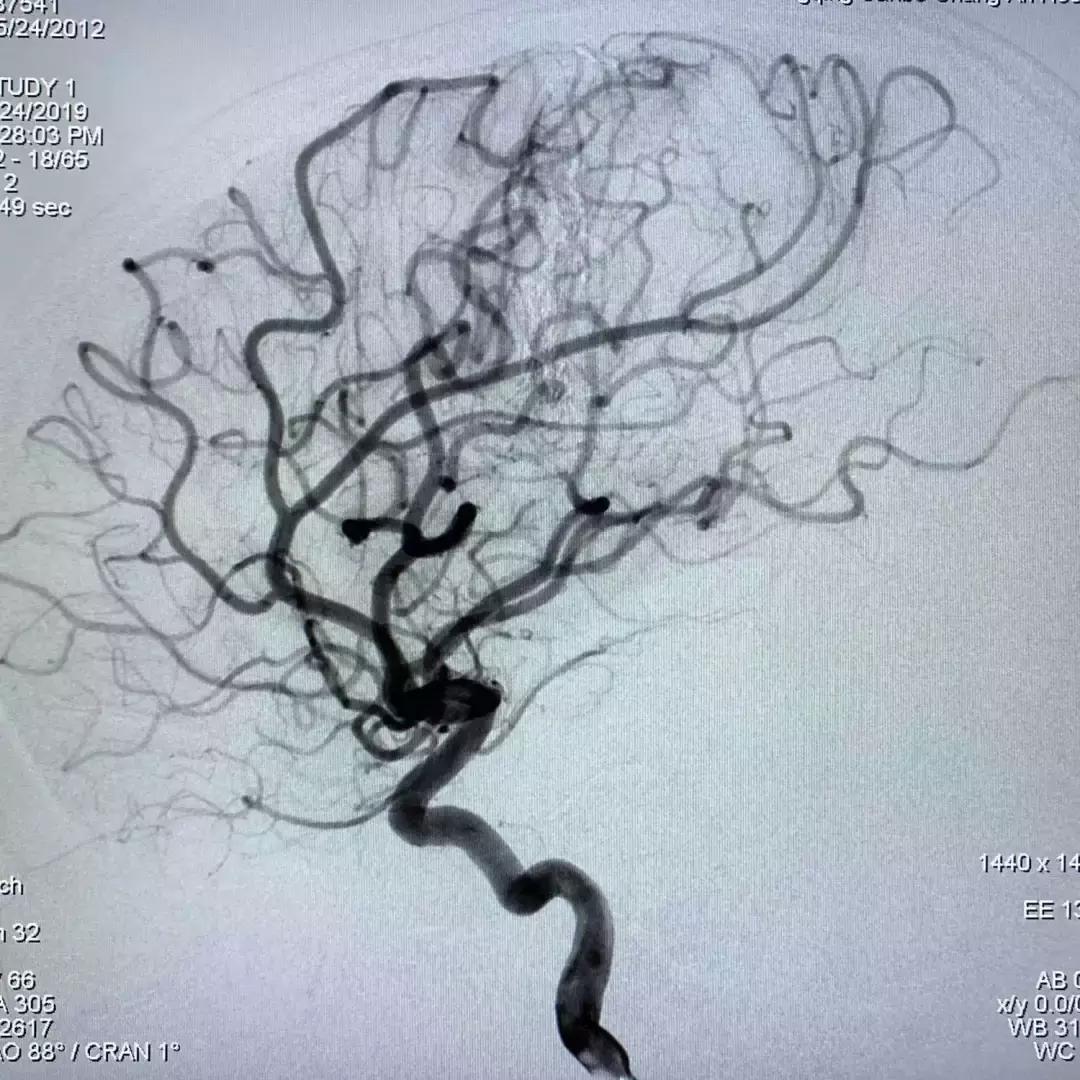

2019年5月24日,经过充分的术前准备,在重庆三博长安医院DSA室,刘加春教授在介入团队的配合下,为小强实施了脑血管畸形栓塞治疗。

刘加春教授反复分析造影。由于畸形的供血动脉真的太细小,而且终末支供血;导管很难超选到位,在超选插管过程中穿破出血的概率较高。最后刘加春教授决定选用最柔软的漂浮微导管来试行寻找合适的栓塞动脉,并不断手推造影了解结构。

如上几图只是刘加春教授寻找合适注胶动脉过程中的一部分